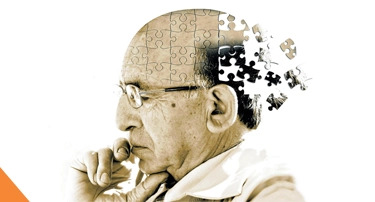

The Impact of Alzheimer's Disease on Memory and Cognitive Function

Alzheimer’s disease is a disorder that is characterized by dementia. Dementia is an umbrella term used to describe a decline in memory, thinking, and daily functioning, while Alzheimer’s disease is the most common cause of dementia.

Exploring the Connection Between Neurology and Alzheimer's Disease

Billions of neurons—specialized cells that process and send information via electrical and chemical signals—are present in the healthy human brain. These cells transmit signals from the brain to the body's muscles and organs as well as between other areas of the brain. When this connection is disrupted by Alzheimer's disease, many neurons stop functioning correctly and eventually die, leading to a widespread loss of brain function.

Dementia Treatment In Jaipur, India

Alzheimer’s disease, the most common form of dementia, in which the individual suffers a gradual loss of psychological abilities, is a global issue. This disturbs memory, thought processing, and other behaviors which compromises the life of the affected individual considerably. Currently, there is no direct remedy for this disease, but if diagnosed in its early stage and adequately managed, the disease’s progression can be controlled. Jaipur India has become an important medical city where different treatments and assisting services for patients with dementia are provided. This blog discusses what dementia is, its possible causes, some of dementia’s symptoms, a treatment that is available in Jaipur, and some of the aspects that cause the treatment’s costs.